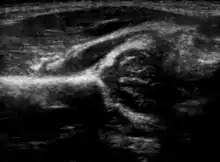

α and β angles used in hip ultrasound

Imaging

Hip dysplasia can be diagnosed by ultrasound[42] and projectional radiography ("X-ray").[43] Ultrasound imaging is generally preferred at up to 4 months due to limited ossification of the femoral head up until then, and is the most accurate method for imaging of the hip during the first few months after birth. However, in most instances, ultrasound screening should not be performed before 3 to 4 weeks of age because of the normal physiologic laxity.[44][notes 1] When universal with targeted ultrasound screening was compared, the former results in an insignificant reduction in the late diagnosis of hip dysplasia, which is why universal ultrasonographic screening of newborn infants is not recommended by the American Academy of Pediatrics.[11]